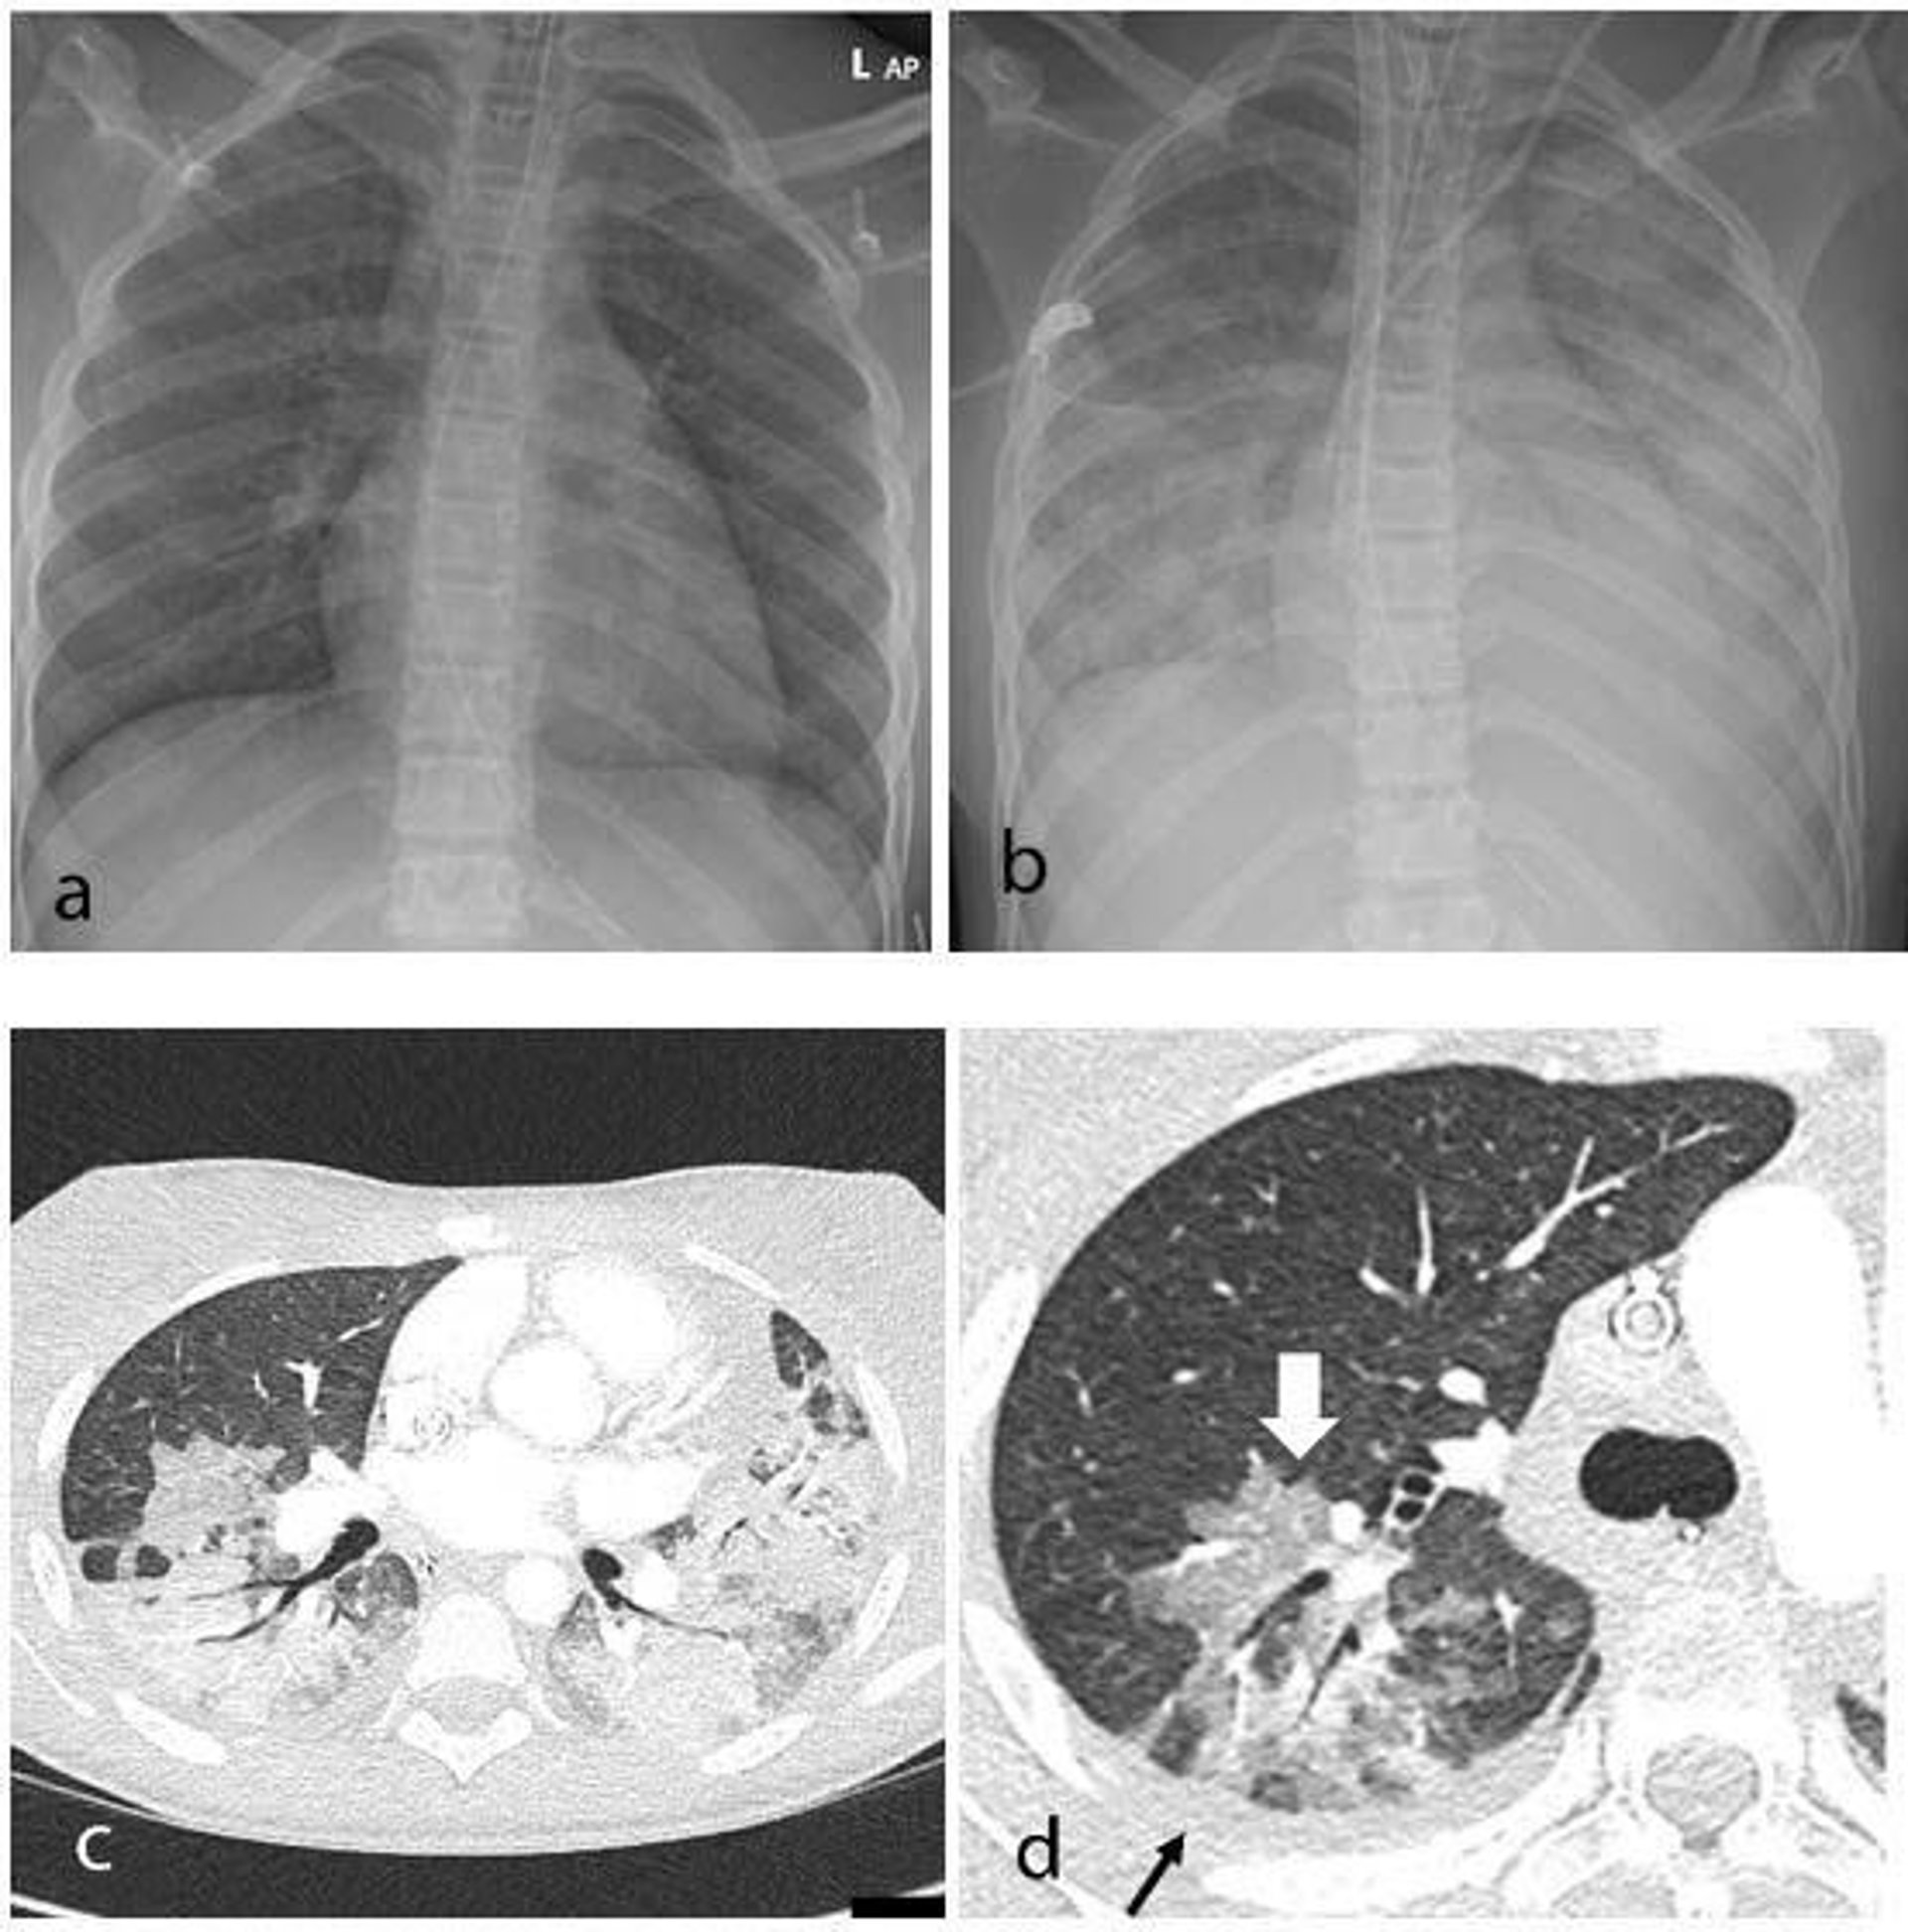

Hallazgos torácicos en una niña de 15 años con síndrome inflamatorio multisistémico en niños (MIS-C).

Hallazgos torácicos en una niña de 15 años con síndrome inflamatorio multisistémico en niños (MIS-C). - RADIOLOGICAL SOCIETY OF NORTH AMERICA

Los 35 niños se sometieron a una radiografía de tórax debido a fiebre, sepsis o características de inflamación multisistémica. Diecinueve rayos X fueron anormales, el hallazgo más común fue el del engrosamiento de la pared bronquial.